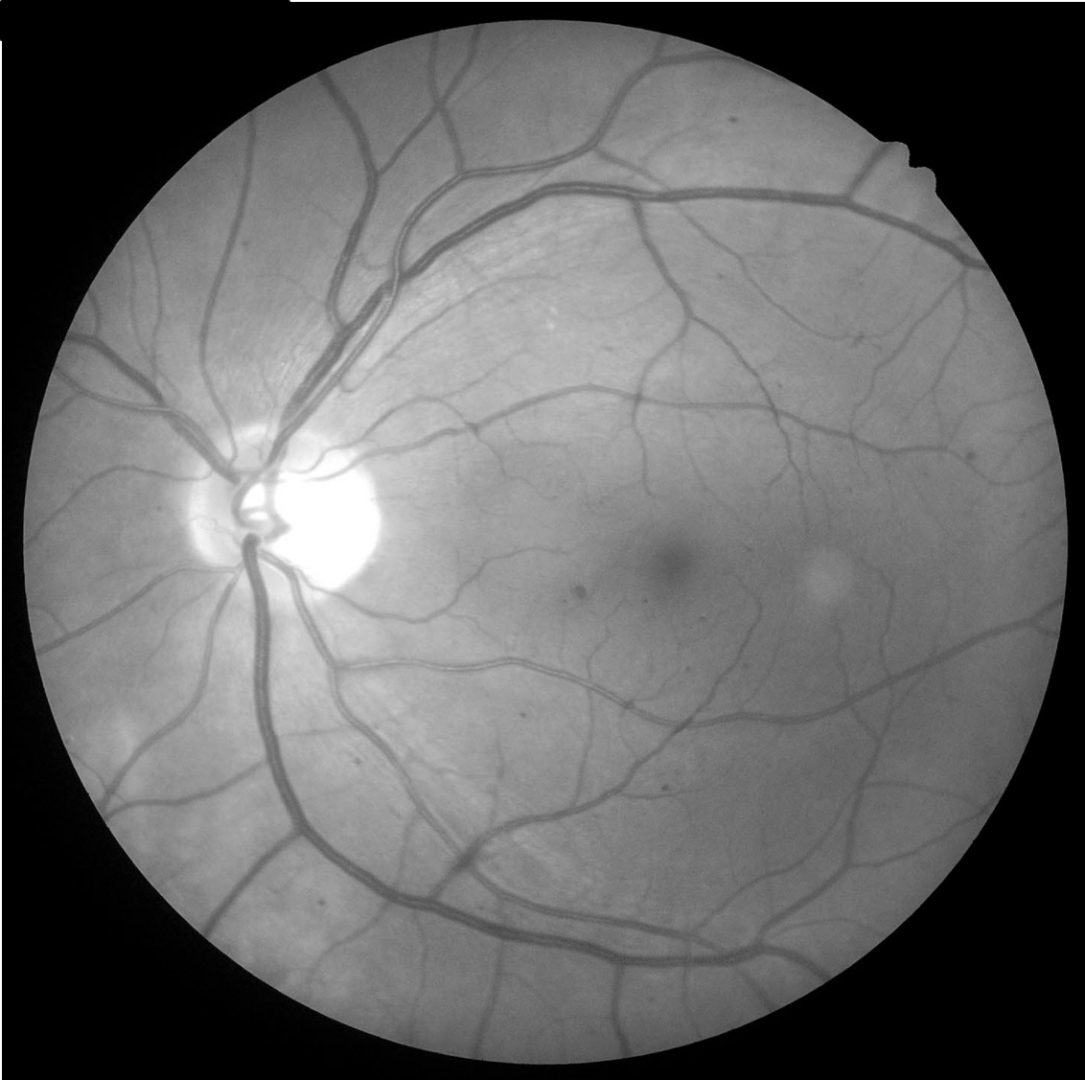

Some examples of each stage of NPDR are below.

Case 1: Mild NPDR

A 72 year old Caucasian female with most recent HbA1c of 7%. She was diagnosed with type 2 diabetes 20 years previously. Her best corrected visual acuity in the right eye is 6/6 (20/20). This case will focus on the right eye only.